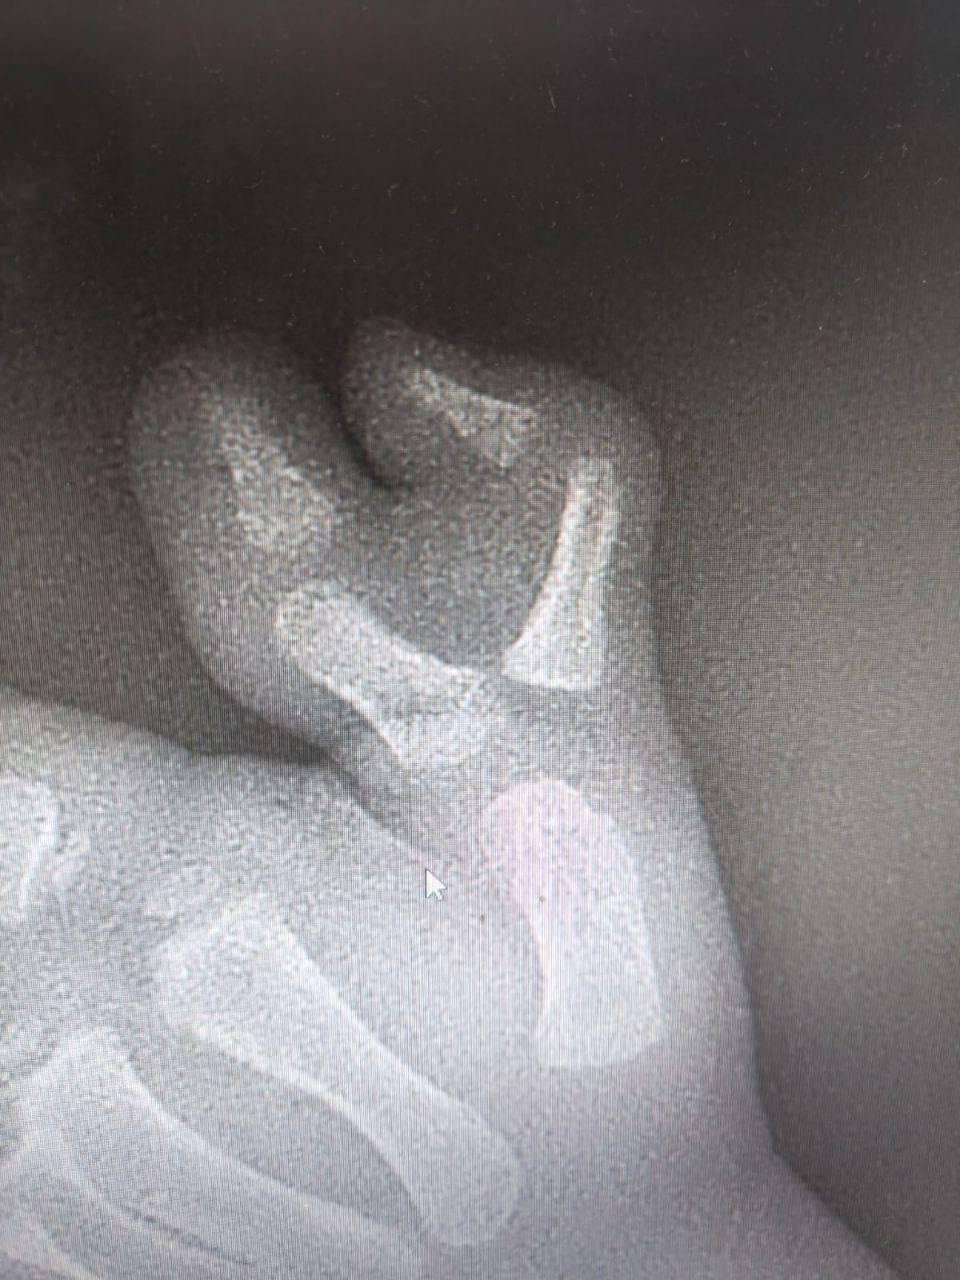

StolicaMedia, 27 ноября 2025. Операция трехлетнего ребенка с шестью пальцами на руке прошла успешно в детской клинической больнице в Подмосковье. Медики удалили добавочный палец, сохранив полную функциональность руки. Об этом сообщила пресс-служба министерства здравоохранения Московской области.

Родители обратились с малышом в травматолого-ортопедическое отделение после того, как заметили, что лишний палец вызывает у ребенка не только физический дискомфорт, но и психологические проблемы. После обследования хирурги выполнили сложную реконструкцию, сформировав правильное анатомическое строение сустава.

Маленького пациента выписали из стационара для дальнейшего амбулаторного наблюдения. Отмечается, что через некоторое время мальчику предстоит плановая процедура по удалению металлоконструкций, после чего он сможет полностью забыть о врожденной аномалии. Операция прошла без осложнений, восстановление протекает нормально.